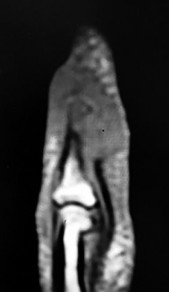

Figures 31a through 31d are the radiographs and MR images of a 52-year-old man who has a 7-week history of right ring finger pain, redness, and swelling. He accidentally stuck his finger with a toothpick 1 week before developing symptoms. There is purulent drainage from the puncture wound site. He was treated with oral antibiotics for 10 days and intravenous (IV) antibiotics for 3 weeks before being seen. Initial cultures grew _Eikenella corrodens_. What is/are the best next step(s)?

This patient had a septic DIP joint that was treated with antibiotics alone. As a result, he developed osteomyelitis with bone destruction and an abscess. The correct answer is debridement of both bone and soft tissue with abscess drainage. Antibiotic treatment without surgery would not successfully eliminate this infection. A bone scan and biopsy are not appropriate because this problem is an infection and not a tumor, and the MR imaging provided enough diagnostic information. Amputation is not indicated prior to an attempt to salvage the digit. Amputation through the DIP joint would not remove the infected bone in the middle phalanx and would provide an inadequate level of resection.